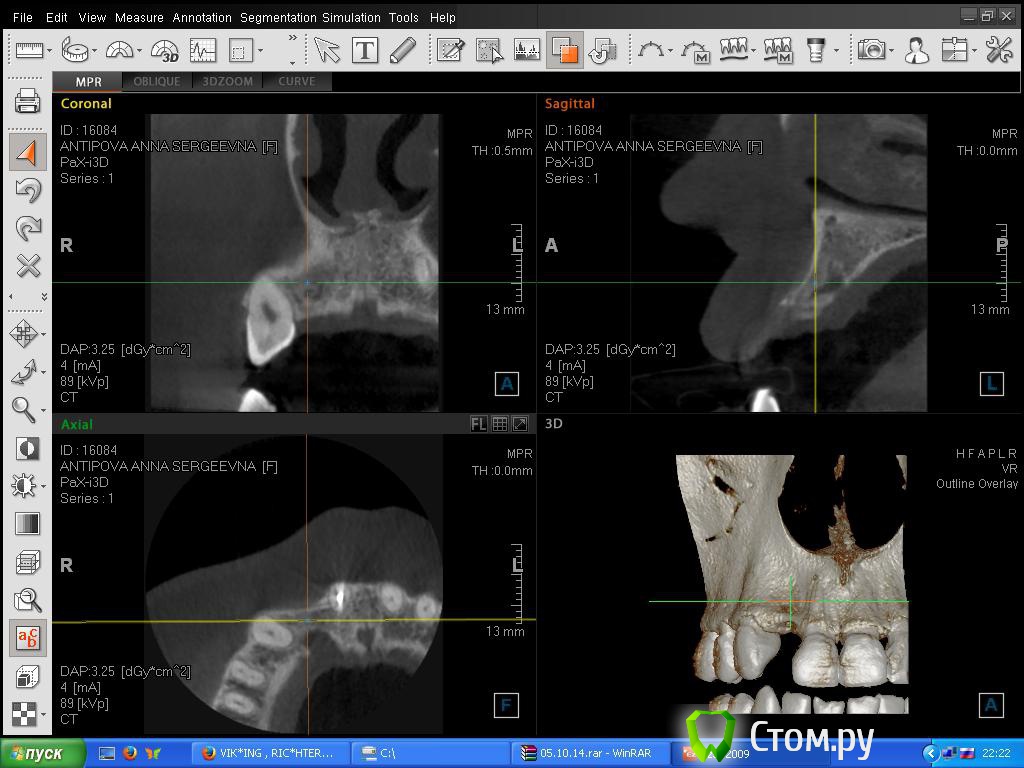

Sorrel Опубликовано 27 октября, 2014 Автор Поделиться Опубликовано 27 октября, 2014 (изменено) Спасибо за советы - про имплант, я в курсе. Просто любопытство. Ну если кто-то выложит нужные срезы в теме, можно будет дать ответ. Мало кто из докторов качает КТшки целиком Сделала картинку, но т. к. я не врач - может и не то что-то.Поэтому Вам лучше знать что смотреть. И как это сделать в данной программе. yadi.sk/i/5VlWzF67cKwPx Изменено 27 октября, 2014 пользователем Sorrel Ссылка на комментарий

Bier Опубликовано 27 октября, 2014 Поделиться Опубликовано 27 октября, 2014 может и можно без костной пластики обойтись, только десневой. 1 Ссылка на комментарий

Sorrel Опубликовано 27 октября, 2014 Автор Поделиться Опубликовано 27 октября, 2014 может и можно без костной пластики обойтись, только десневой. Спасибо, за ответ. Еще скажите, темное пятно с внутренней стороны (киста была) - это же не отсутствие кости? Там все нормально? + врач измерял толщину кости - 6 мм (но по нижнему краю, не там, где сужение спереди) - это тоже нормально? Ссылка на комментарий